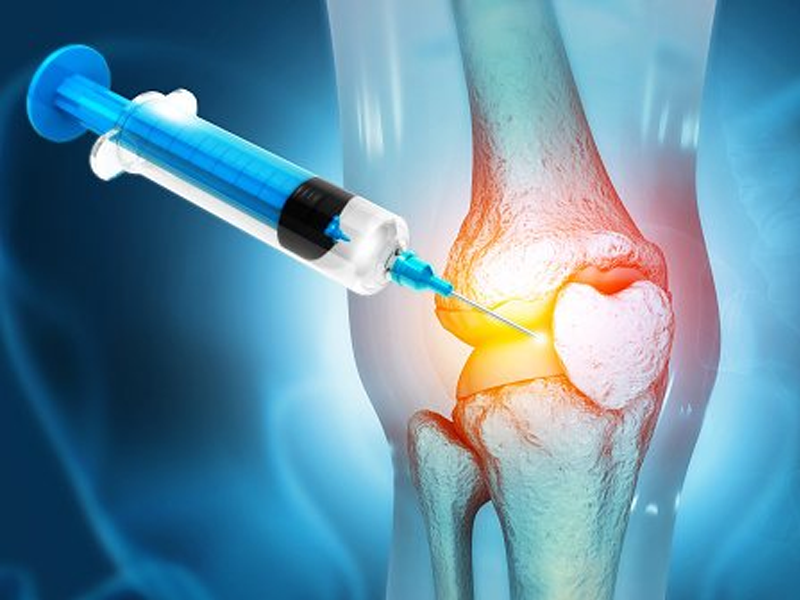

تزریق ژل هیالورونیک به زانو (Hyaloronic acid) یک روش جدید و کمتهاجم برای درمان درد های زانو است و بیشتر برای بیمارانی تزریق میشود که آرتروز خفیف یا متوسط دارند. هیالورونیک اسید یک ماده ی طبیعی است که به طور طبیعی در مایع مفصلی زانو